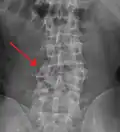

A burst fracture is a type of traumatic spinal injury in which a vertebra breaks from a high-energy axial load (e.g., traffic collisions or falls from a great height or high speed, and some kinds of seizures), with shards of vertebra penetrating surrounding tissues and sometimes the spinal canal.[1] The burst fracture is categorized by the "severity of the deformity, the severity of (spinal) canal compromise, the degree of loss of vertebral body height, and the degree of neurologic deficit."[2] Burst fractures are considered more severe than compression fractures because long-term neurological damage can follow. The neurologic deficits can reach their full extent immediately, or can progress for a prolonged time.

Diagnosis is by medical imaging.